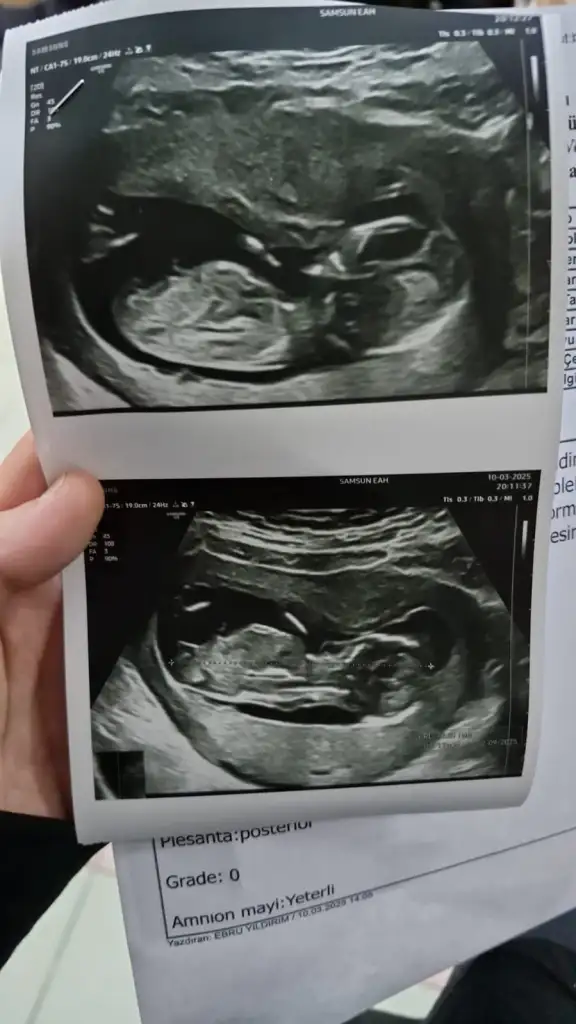

Erkek gibi geldi bana.2 li taramadan ultrason goruntum tahmin edebilecek olan var mi Eki Görüntüle 3575150

Başka açıdan var mı burda pek tahmin yürütemedimBanada bakarmısınız lütfen tahminde bulunurmusunuz

Sadece bu varBaşka açıdan var mı burda pek tahmin yürütemedim